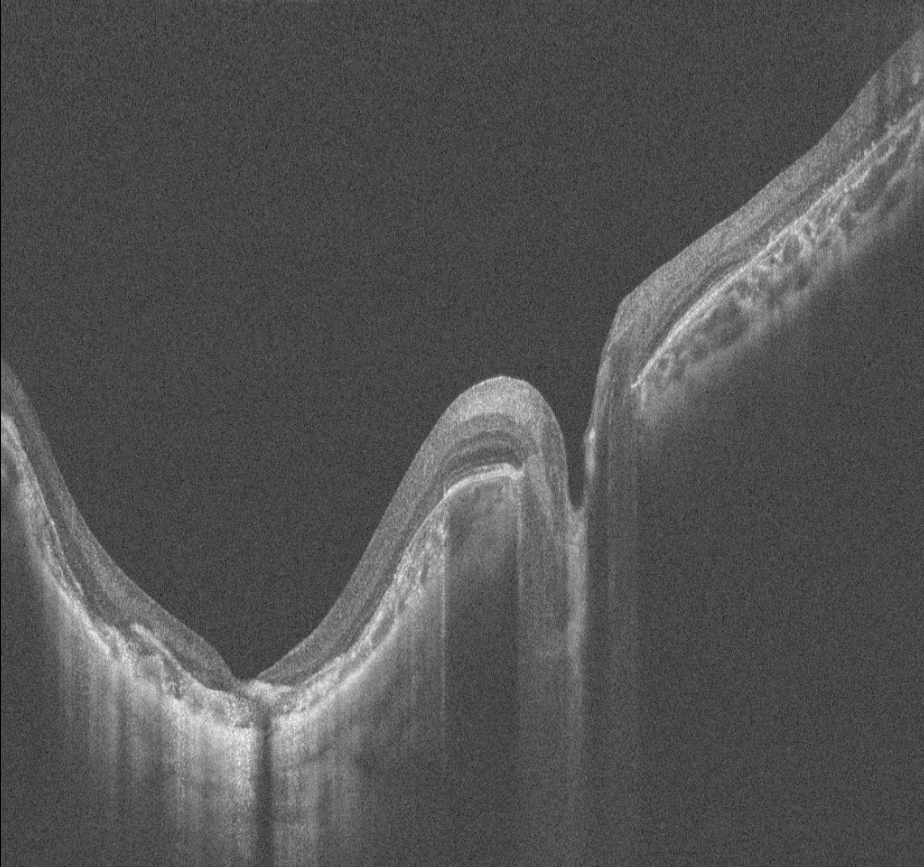

14 yaşındaki erkek hasta bebeklikten bu yana görme kaybı öyküsü ile kliniğimize başvurmuştur. Ailenin tek çocuğudur, anne baba arasında akraba evliliği öyküsü mevcuttur ve her iki gözde görme 1 mps düzeyindedir. Hastanın renkli fundus, FAF ve OCT görüntülerini görmektesiniz. Lütfen cevabınızı aşağıya yazınız.